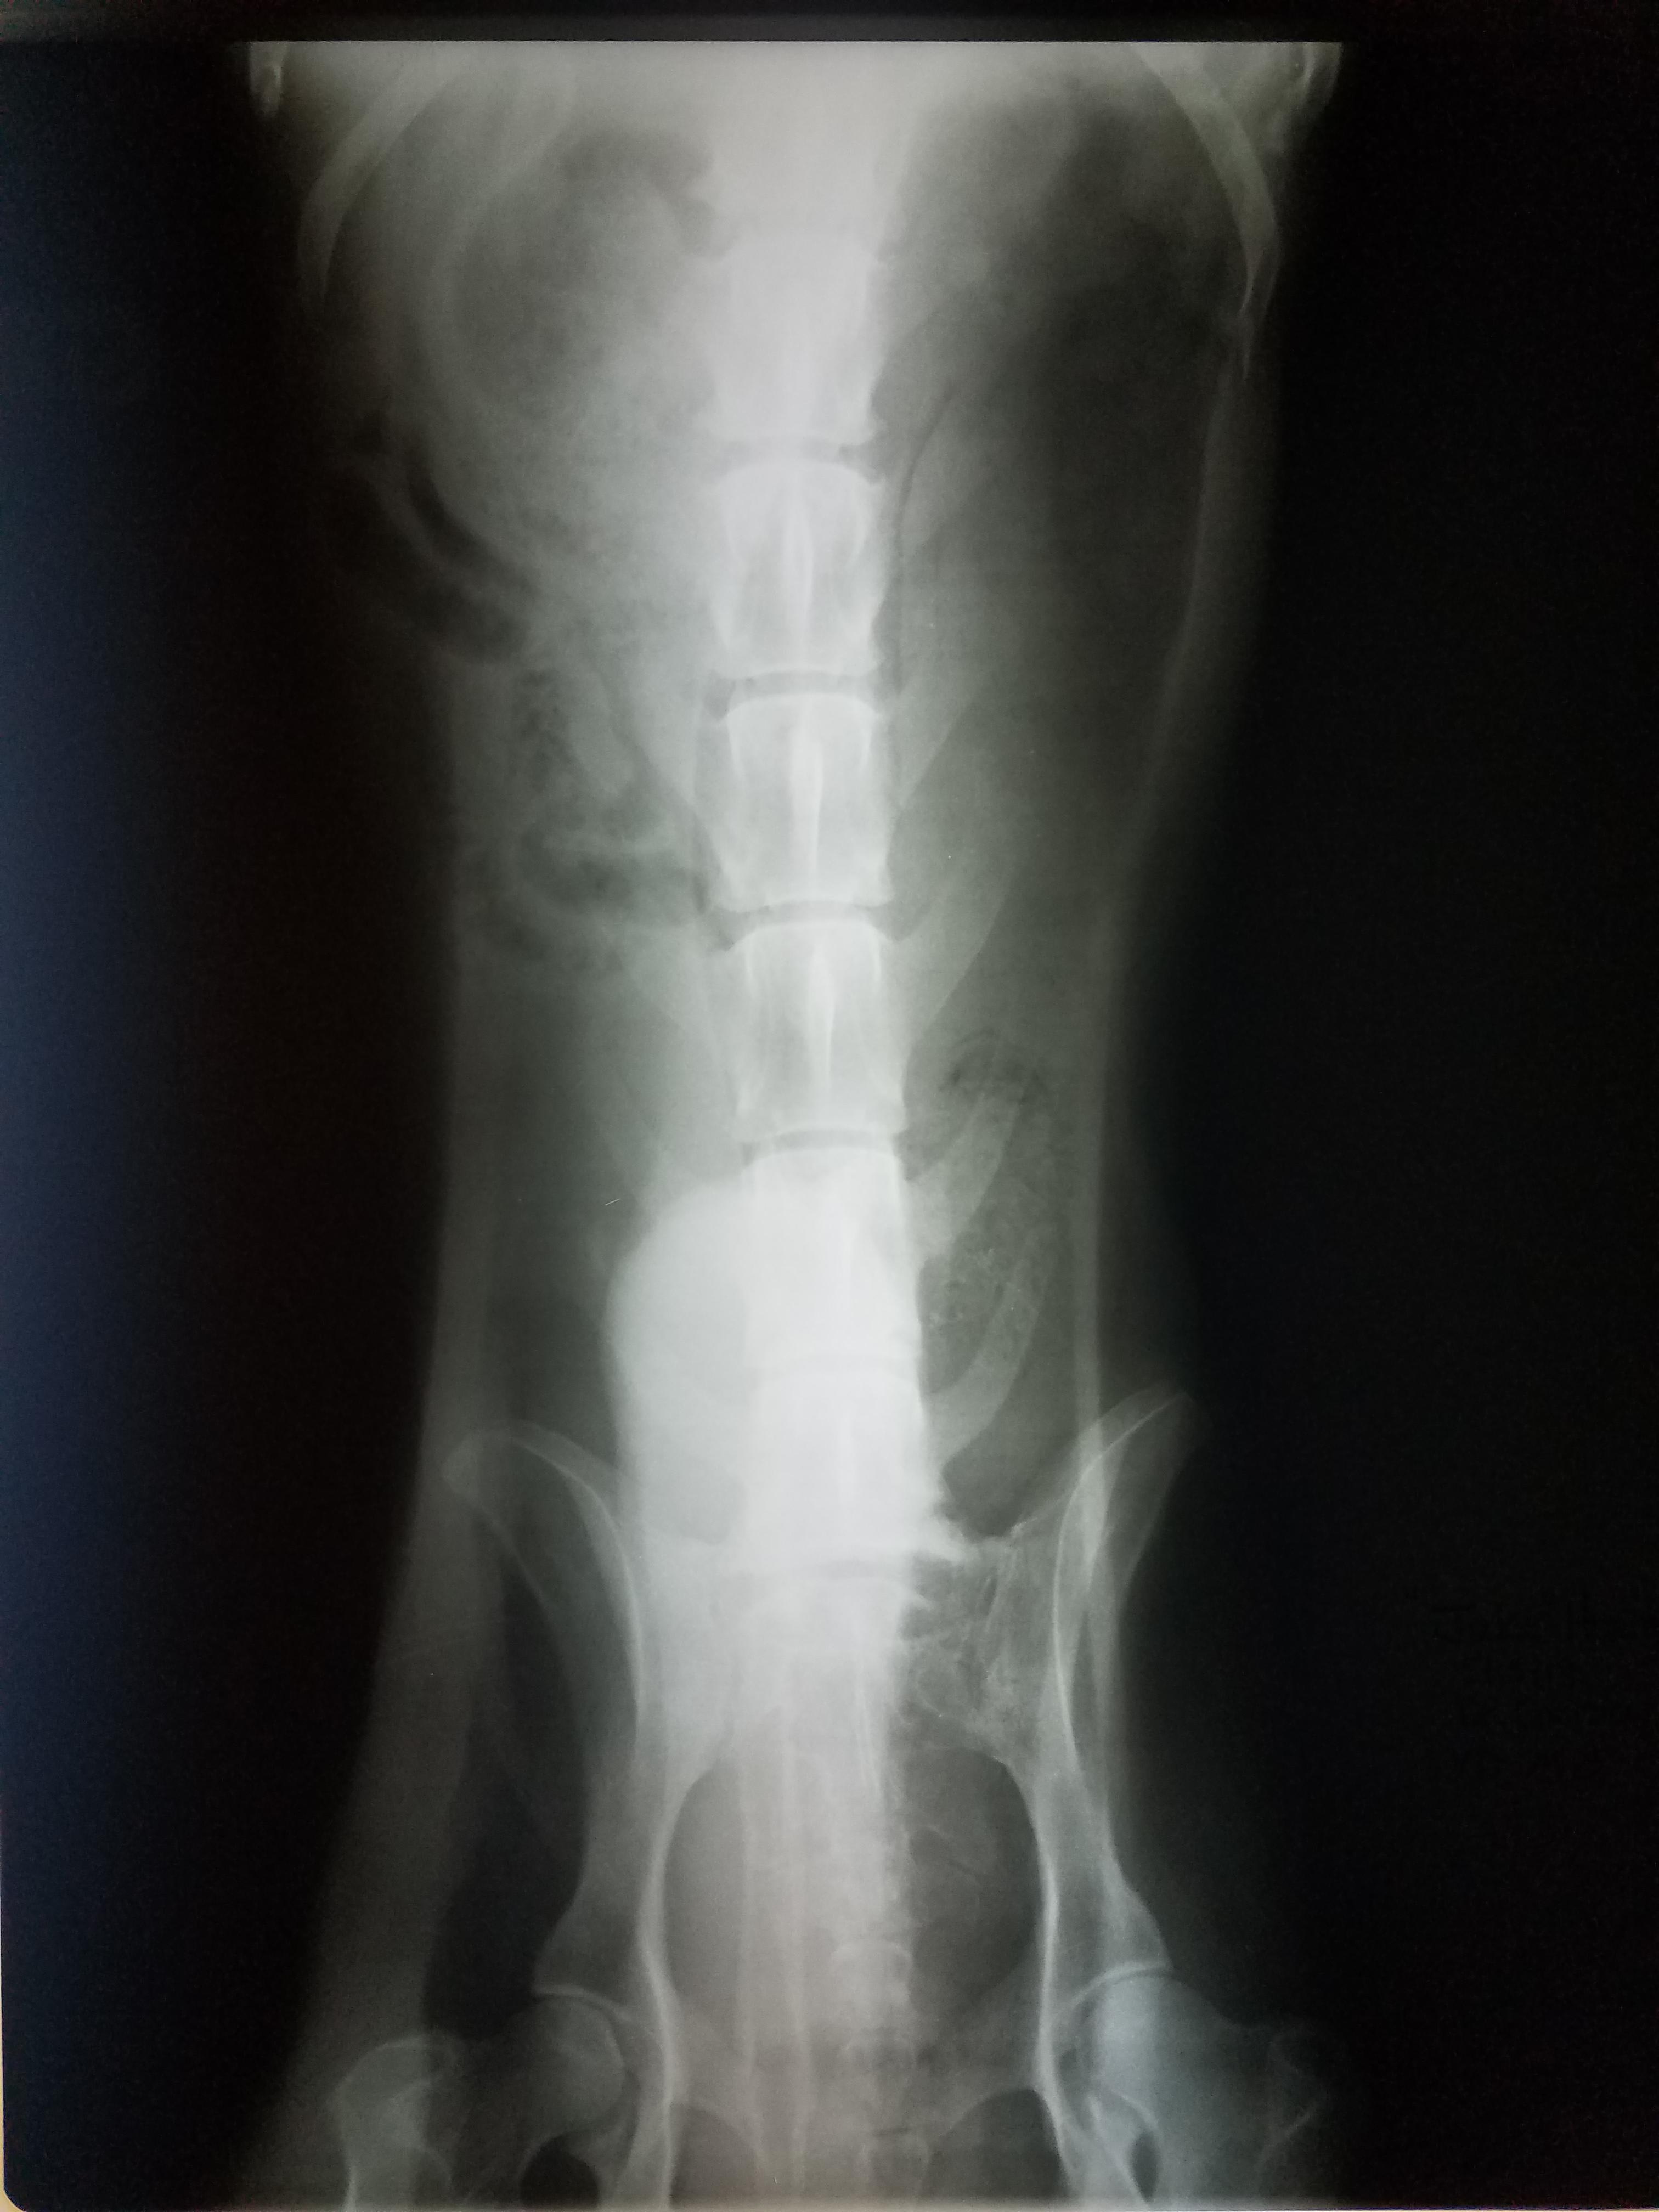

Pet's info: Dog | German Shepherd | Male | unneutered | 3 years old | 119 lbs

This an x-ray focused on the caudal abdomen. As far as I can see there is moderate distension of the last part of the intestine (colon) which is filled with feces and gas. There are no other abnormalities and the radiopacity on the ventro-dorsal view is due to an artifact rather than an actual abnormality.